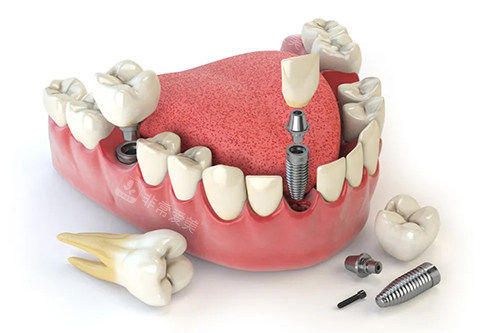

牙齿种植牙模型卡通示意图

种植牙的核心部分便是种植体,它直接关系到种植牙的稳定性和使用寿命。

榆林中诺口腔医院采用的是进口种植体,这些种植体均来自国内外比较有名品牌,经过了严格的质量检测和大量的临床验证。

而且,优质的进口种植体表面经过特殊处理,能够促进骨细胞的生长和分化。

一些种植体表面采用了纳米技术,增加了种植体与骨组织的接触面积,提高了骨结合的速度和质量。

这意味着患者在植入种植体后,能够更快地实现骨结合,缩短修养时间。